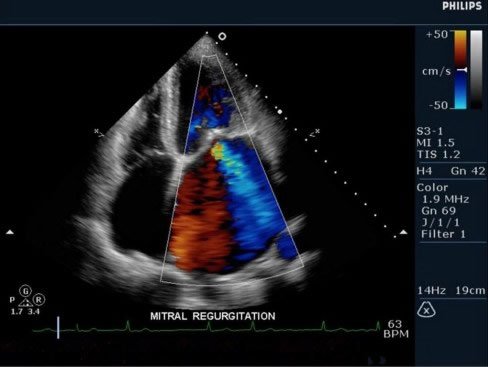

• Ecodoppler cardíaco: Com ele, o especialista pode analisar o fluxo intracardíaco, sendo essencial para diagnosticar doenças valvulares.